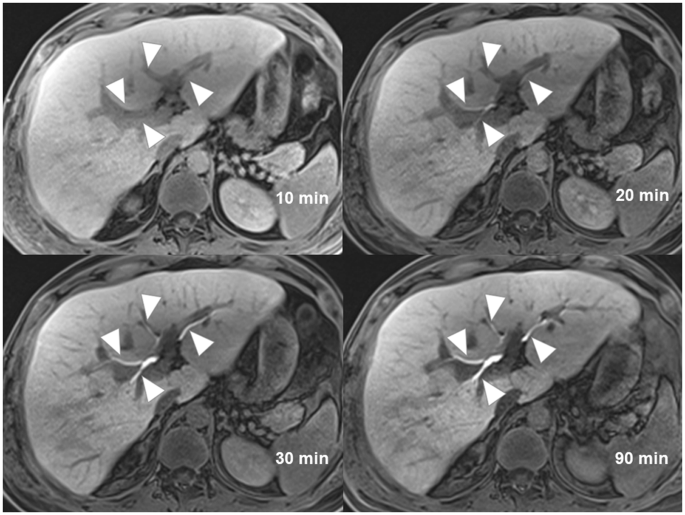

Biliary tree visualization on CEMRC

In Table 1, the mean score of biliary tree visualization on CEMRC acquired at 10, 20, 30 and 90 minutes were 2.96, 4.17, 4.29 and 4.30 respectively. The inter-rater reliability was good to excellent with ICC of 0.921, 0.787, 0.717 and 0.930 on CEMRC acquired at 10, 20, 30 and 90 minutes respectively. The best biliary tree visualization was scored on CEMRC acquired at 90 minutes (Fig. 1) and this was substantiated by the best inter-rater reliability test. On the contrary, the poorest biliary tree visualization was scored on CEMRC acquired at 10 minutes by all readers, and it was also supported by an excellent ICC.

A 36-year-old man with liver injury (not shown). Images of contrast enhanced MR cholangiography acquired at 10 minutes, 20 minutes, 30 minutes and 90 minutes show progressive improvement of intrahepatic bile ducts visualization (arrowheads) from very poor visualization at 10 minutes to excellent visualization at 90 minutes. The average scores given by three readers are 1.00 (10 minutes), 4.00 (20 minutes), 4.67 (30 minutes), 5.00 (90 minutes).